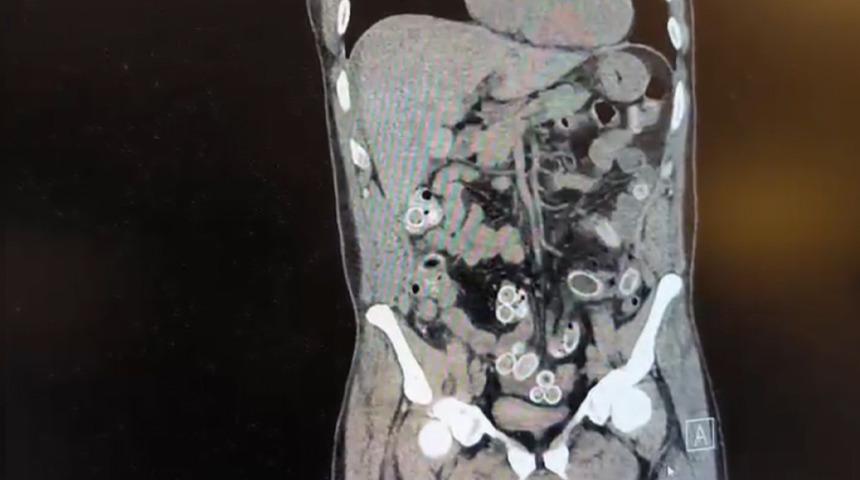

İhbar üzerine çalışma başlatan Beşiktaş Asayiş Büro Amirliği ekipleri, doktorlarla görüşme gerçekleştirdi. Doktorların değerlendirmesi sonrası ameliyata alınan Cüneyt Ç.’nin bağırsaklarından, toplam ağırlığı 259,7 gram olduğu öğrenilen 49 esrar macunu çıkarıldı. Şüpheliye ait 1 adet cep telefonu da hastane yetkilileri tarafından polis ekiplerine teslim edildi.